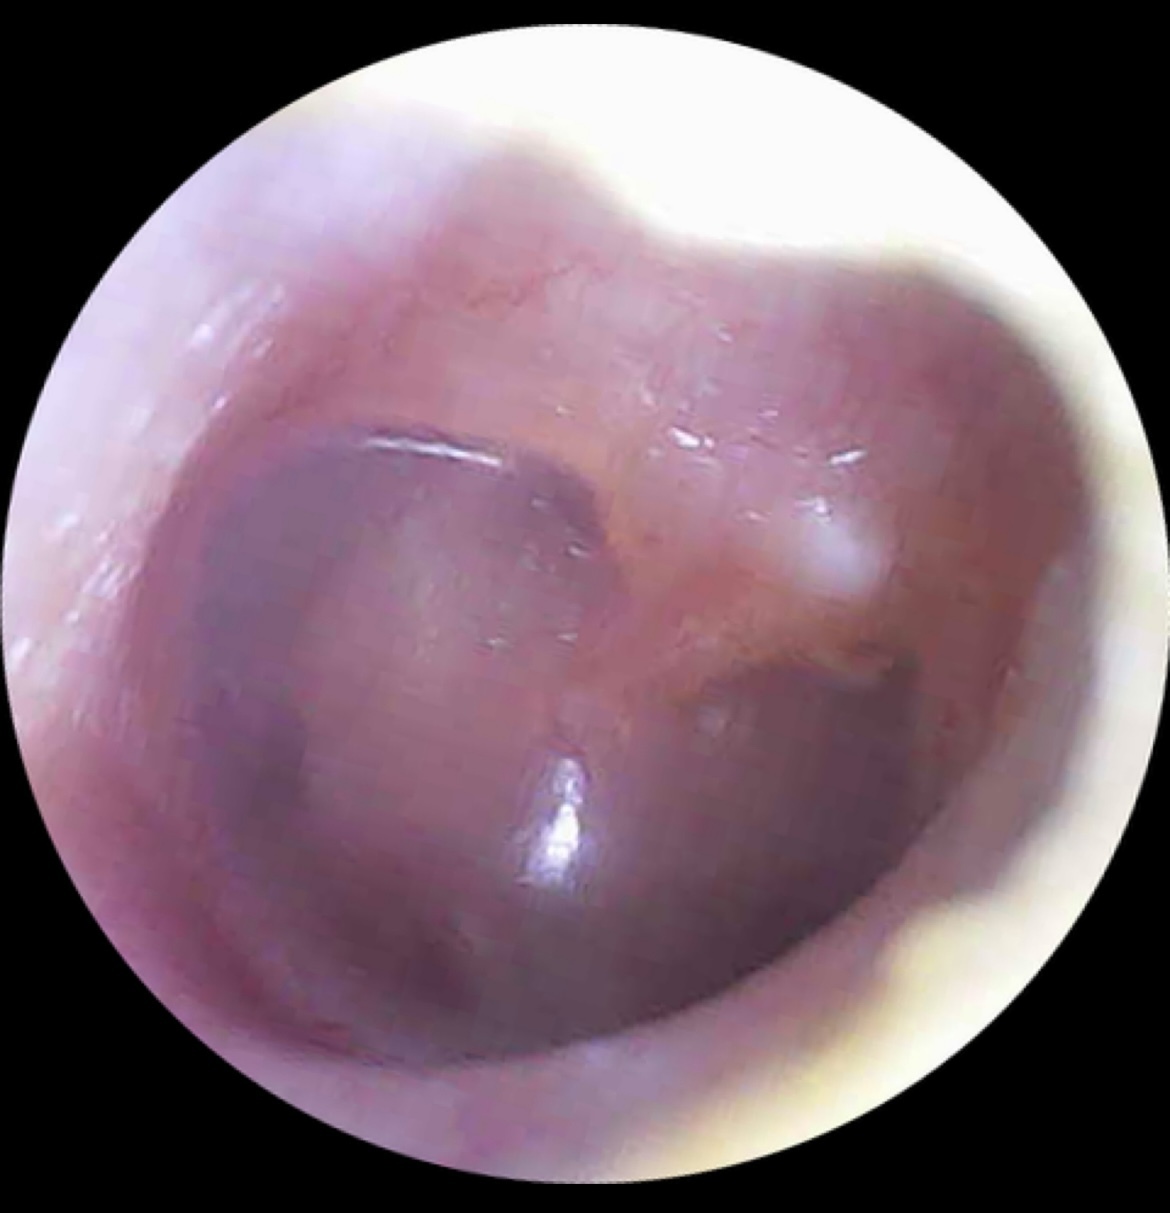

Острый катаральный средний отит. Не требующий антибиотиков! Даже если болит. Антибиотики - не обезболивающее. Нужно бдительное наблюдение и врач на связи.

Экссудативный средний отит. Скопление НЕгнойной жидкости в ухе. Бывает после гнойного отита, на фоне долгих насморков и потому что потому.

Видя соответствующую картину мы, врачи и уже прокачанные пациенты, понимаем наш маршрут. К врачу, наблюдать, сдавать анализы, ехать и больницу и др. Абстрактная «боль в ухе» переходит в реальную картинку и объективизируется.

А еще! Это помогает наблюдать уши в динамике, особенно если смотрят разные врачи и надо выстроить единую картину.